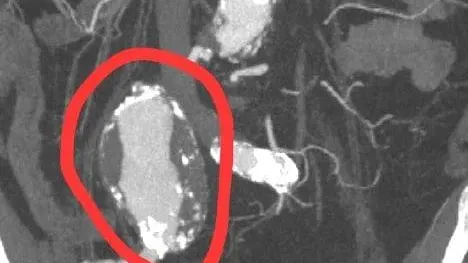

Пожилой мужчина поступил в больницу в Раменском с жалобами на боль в пояснице и при мочеиспускании. В ходе диагностики у него выявили гигантскую аневризму правой общей подвздошной артерии. Состояние угрожало жизни пациента из-за риска кровотечения.

Как рассказали в областном Минздраве, мужчине провели срочную операцию. Диаметр аневризмы составлял 6,5 сантиметра. Пораженный участок восстановили при помощи синтетического протеза.